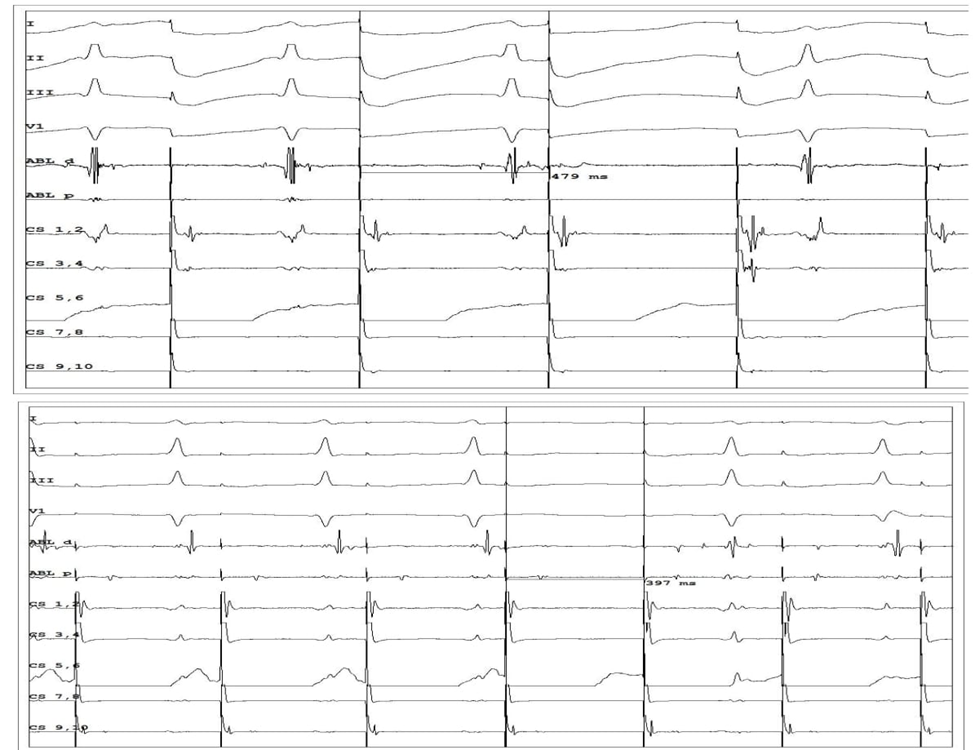

პროცედურის შემდეგ პაციენტს ჩაუტარდა ელექტროფიზიოლოგიური კვლევა, რომლის საშუალებითაც განხორციელდა გამტარებლობის აღდგენის განსაზღვრა მილიწამებში. სურათ 5-ზე ჩანს თუ როგორ გაუმჯობესდა AV კვანძის გამტარებლობა კარდიონეიროაბლაციის ჩატარების შემდეგ ვენკენბახის პერიოდების ხანგრძლივობის შემცირებით (480 – 400 მწმ).

სურათი 5. ვენკენბახის პერიოდები CNA პროცედურამდე და პროცედურის შემდეგ

წარმატებული მკურნალობის შემდეგ პაციენტს უტარდებოდა 24 თვის განმავლობაში ეკგ მონიტორინგი 3 თვიანი ინტერვალების სახით. დაკვირვების საფუძველზე შეიძლება ითქვას, რომ ეკგ-ზე გამტარებლობის შეფერხება არ აღინიშნება. (იხ. სურათი 6)

სურათი 6. გულისცემის ყველაზე მაღალი და დაბალი სიხშირის დროს პაციენტის ეკგ